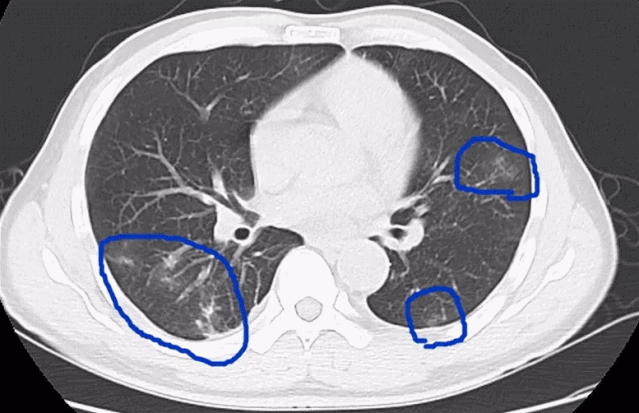

在医院检查发现,3人的血常规中嗜酸性粒细胞明显升高。经过寄生虫抗体、CT等检查,他们都被诊断为“肺吸虫病”。